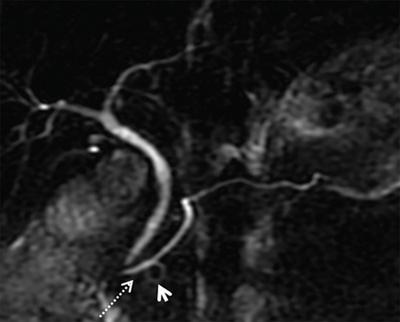

Ansa pancreatica

• Ansa pancreatica is seen when there is obliteration of the dorsal pancreatic duct at the junction with ventral duct, and instead, the proximal portion of the dorsal duct connects with an inferior side branch of the ventral duct through an S-shaped collateral duct.

Image

MRCP image of ansa pancreatica in a 43-year-old male. The proximal dorsal duct connects with an inferior branch of the ventral duct (dashed arrow) through S-shaped collateral. (arrowhead)